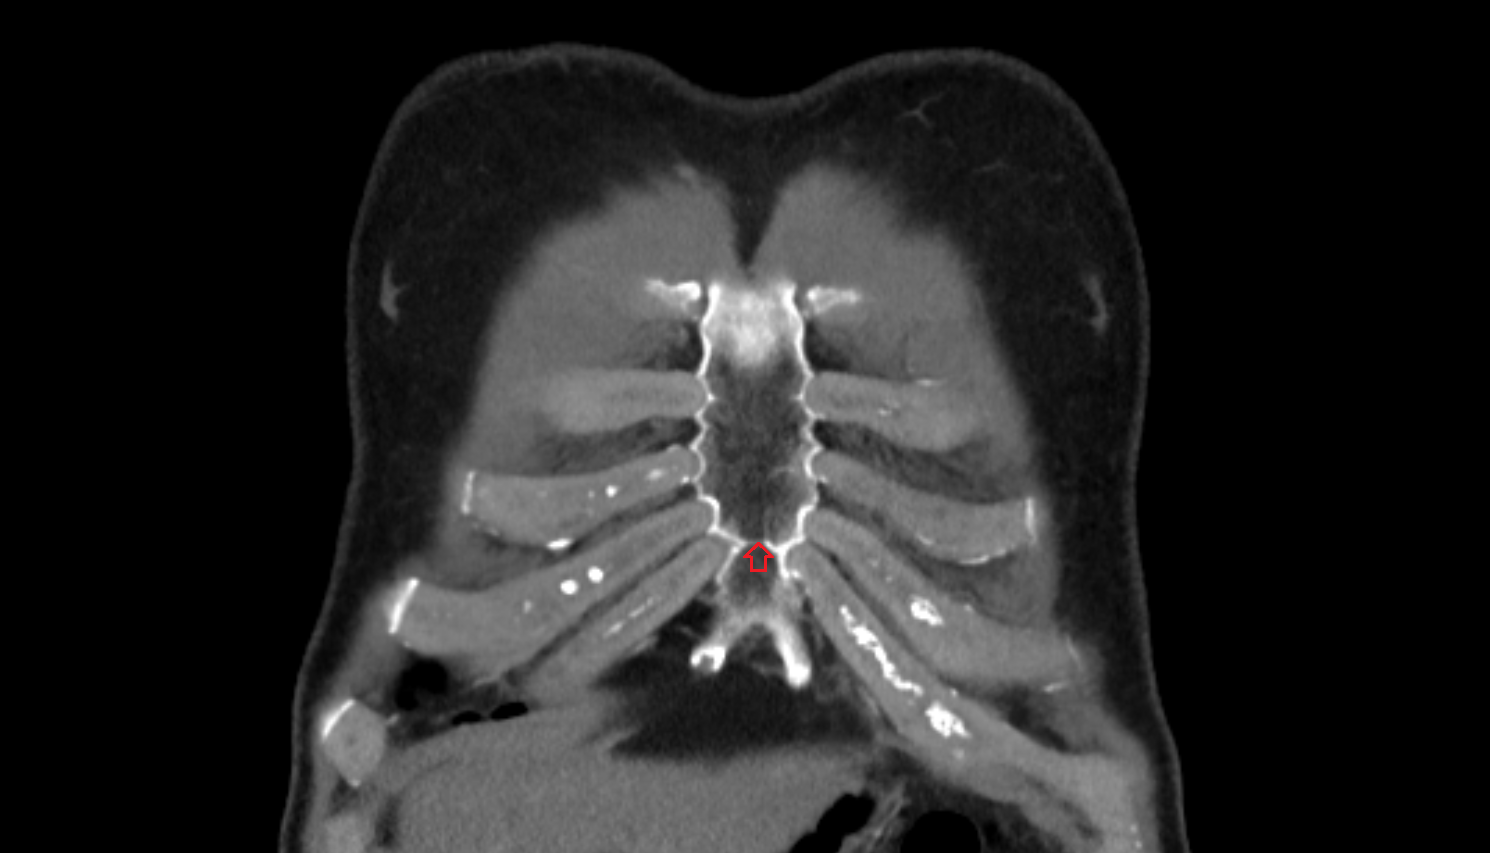

- Manubrium of sternum

- Body of sternum

- Xiphoid process of sternum

- Sternum

- Costal cartilages

- Costal notches

- Costochondral joints

- Sternocostal joint

- Sternocostal synchondrosis of first rib